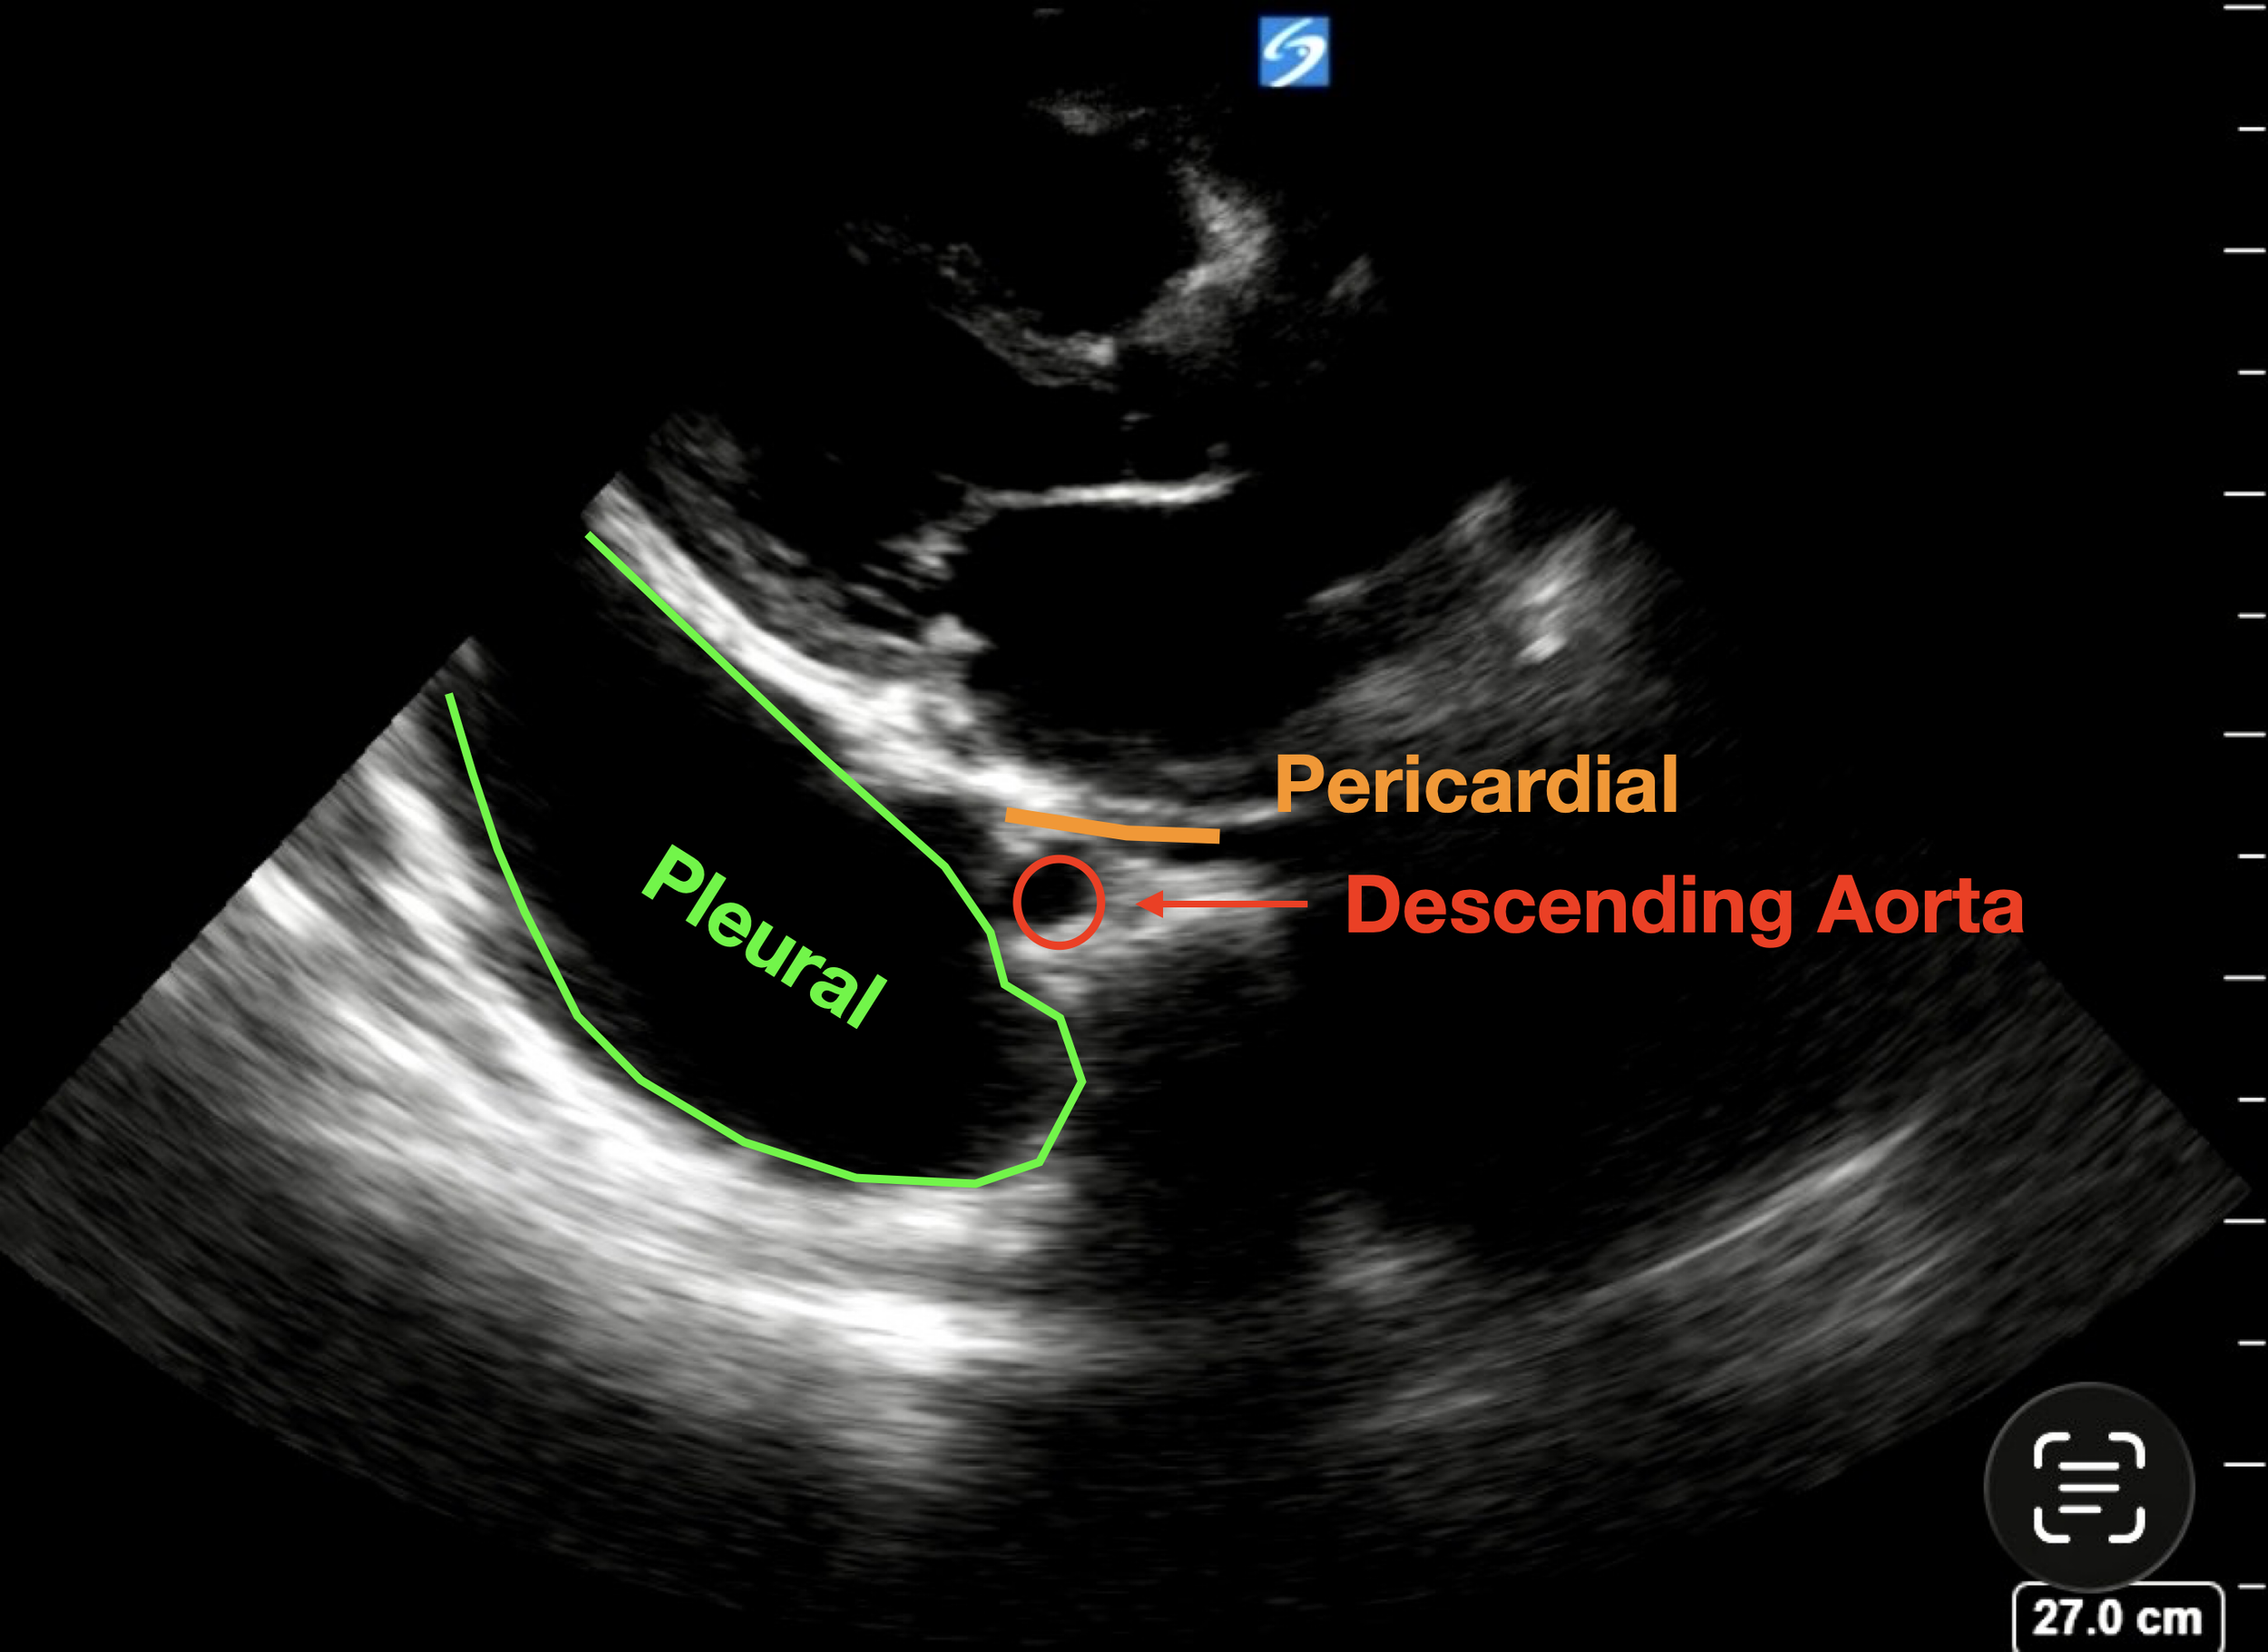

Basic POCUS: the initial PLAX

In the top image the heart can be seen sitting in the top third of the screen. In the bottom left of the screen there is a large left-sided pleural effusion (extending towards the LV apex). There is also probably a large right pleural effusion sitting on the bottom right of the image. These effusions could be easily missed if the depth was not set deep enough on the initial view.

There is possibly a trace pericardial effusion sitting above the pericardium but it is trivial.

An important structure to visualise is the descending thoracic aorta - which is the small circular structure just below the left atrium. If you remember from previous cases (see bottom picture):

• Pleural Effusions track behind (deep to) the descending aorta (green)

• Pericardial Effusions track in front of (superficial to) the aorta (potential space in orange line)

The bottom clip is exactly the same view, but with the depth reduced to focus on the heart itself - note how you can still see the bright line behind the pleural effusion, but if the depth was reduced any further it would easy to miss the pleural effusion.

In this view we can see:

• No significant pericardial effusion (the effusion tracks behind the aorta so is pleural)